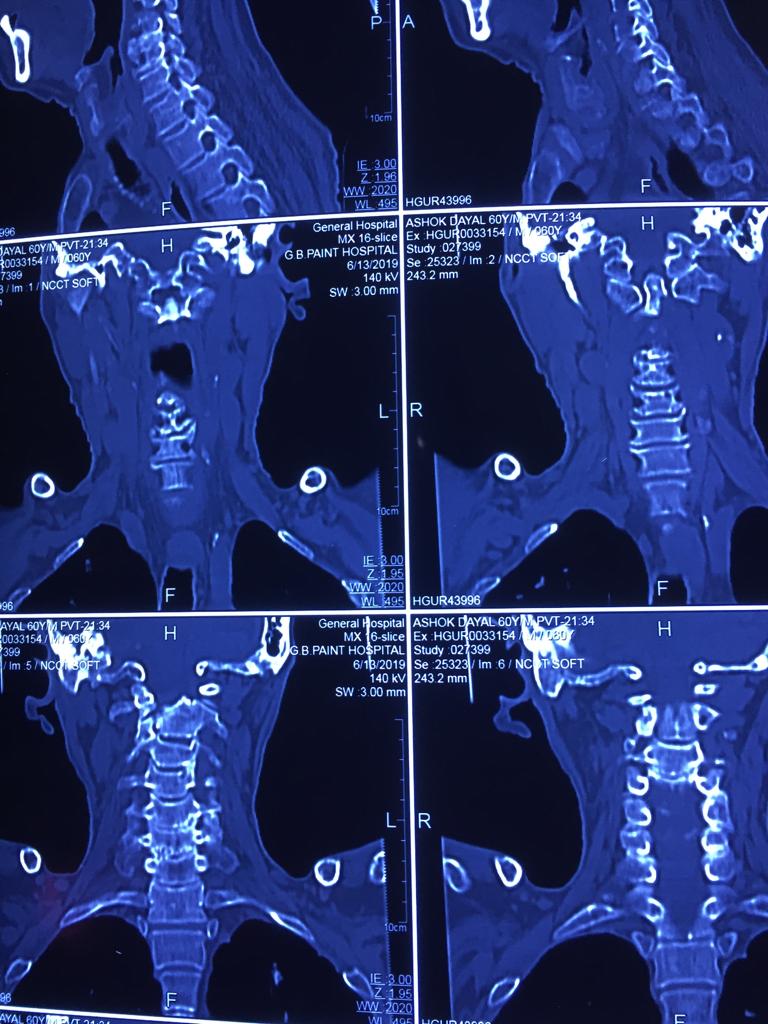

Cases